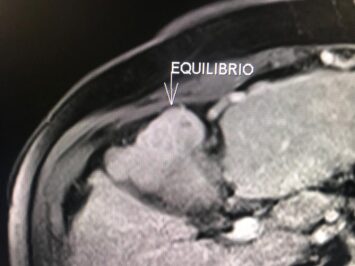

En el presente caso, encontramos una lesión típica de hepatocarcinoma en el segmento 5 ( hiperintensa en T2, restringe en la Difusión con ADC bajo. Realza heterogéneamente postcontraste EV, con wash out y presencia cápsula tardía).